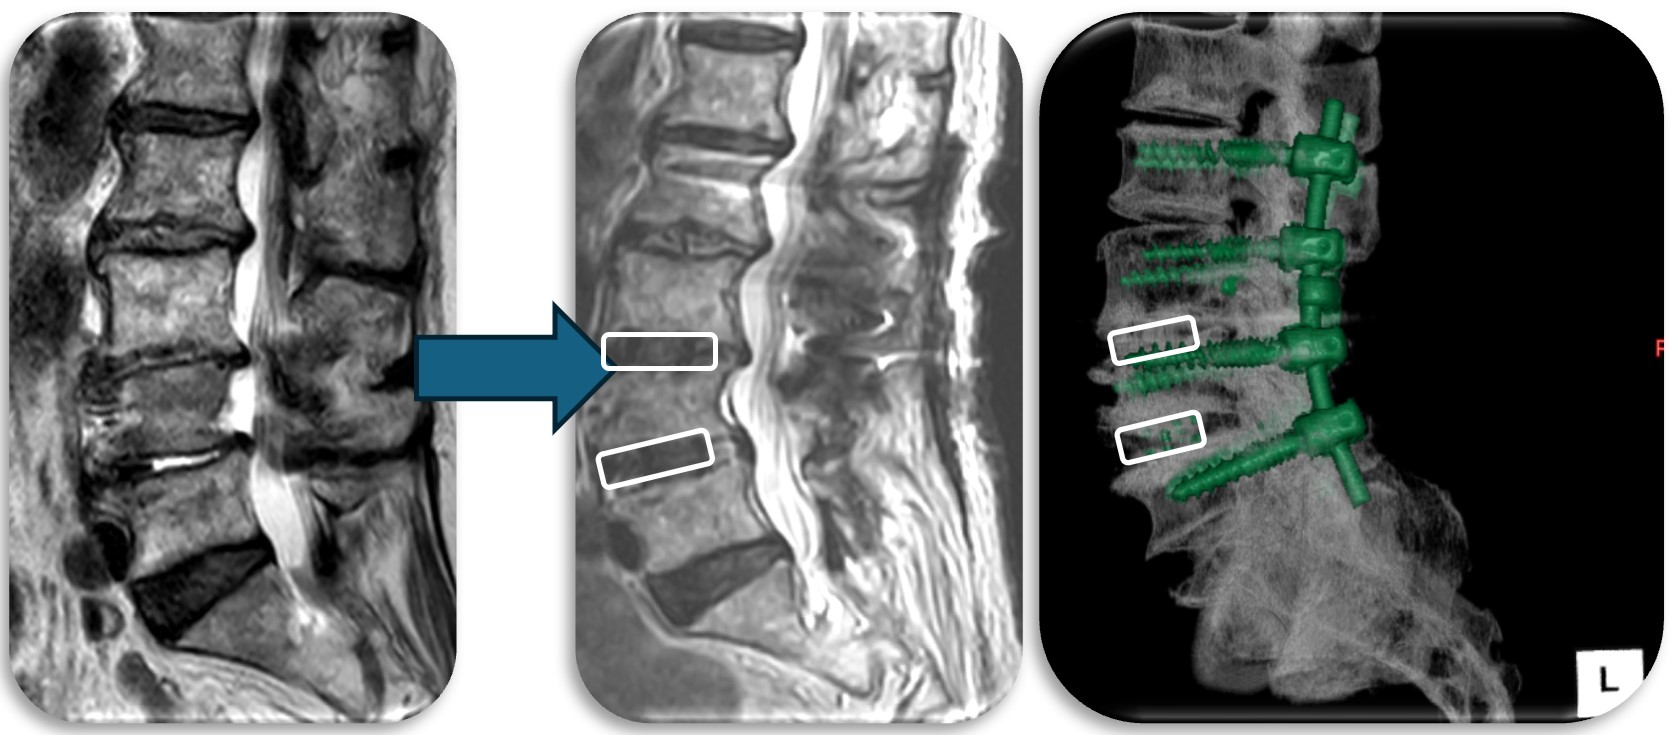

(代表例③)

腰部の脊柱管狭窄症に対して、腰の側方から徐圧し、後方から固定術(OLIF)した症例です。椎間板が摩耗していたり、不安定性がある症例、後方からの手術歴があり再手術症例に適した手術方法です。狭小化した椎間板にスペーサーを挿入(白線)する事により、脊柱管の高さを正常な状態に戻し3次元的に狭窄を改善させます。